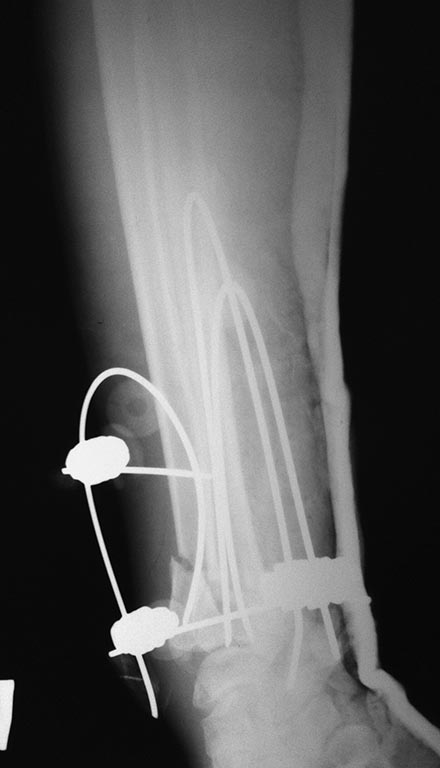

Здравствуйте, уважаемый коллега! К этой спице фиксируются изогнутые спицы, создающие тем самым напряжение. И еще, она проходит трансфрактурно, через внутрисуставной перелом лучевой кости.

В отверстие, произведенное сверлом 2,5, вводится 2мм спица у которой загнут только конец, а остальная часть прямая. И только после достижения желаемого результата, т.е. спицы в метафизе с допустимой репозицией, спицы сгибаются с сохранением пружинящего эффекта и фиксируются к дист. спице. Как мне кажется, напряжение в спицах должно быть.

Поперечная спица (дистальная, как я понял) изогнуться не должна. Силы напряжения, фиксированных к ней спиц, реализуются по ее оси. Проще говоря, они эту спицу растягивают, а не гнут.

А проксимальная поперечная спица в локтевую кость добавлена, чтобы спицы лучевой кости не вытянули дистальную в лучевую сторону. В таком случае связующий узел с локтевой стороны мог упереться в головку локтевой кости и "организовать" там пролежень.